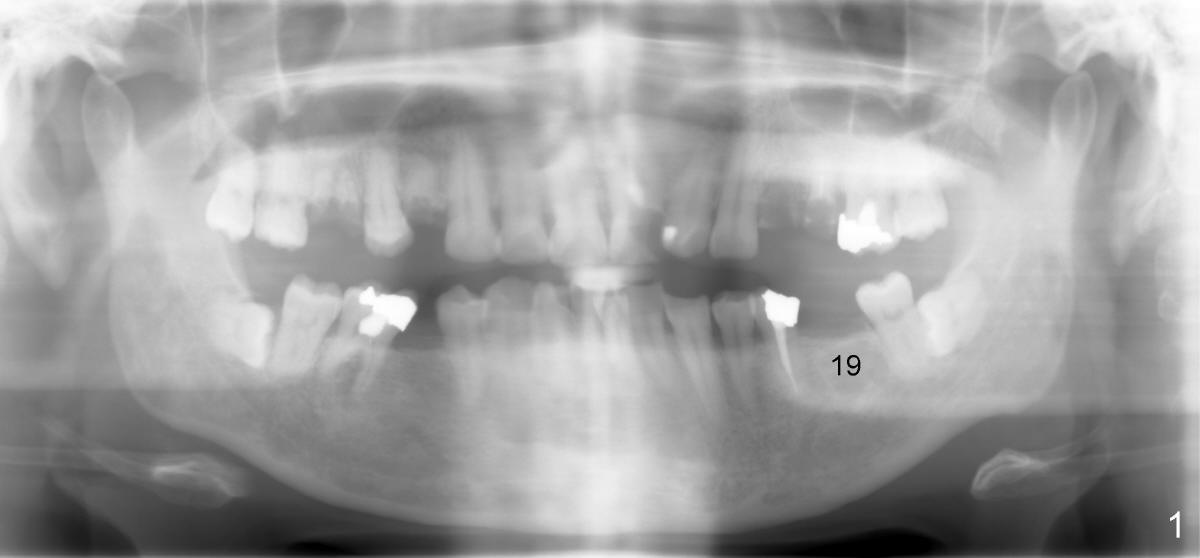

Mr. Zhou is in his fifties. Finally he starts implant restoration. But he has financial constraint. It appears that implant restoration at the site of #19 is the most rewarding in term of restoration of his mastication with a single implant (Fig.1). The implant is apparently placed at the proper level (Fig. 2: I, 6x17 mm). The implant is osteointegrated with minimal bone resorption at crest six months later (Fig.3). The teeth #15 and 18 cannot occlude when 4.5x5 mm abutment (Fig.4: A) is placed at #19 implant (<). It takes a while to trim the unipost from the top gradually in order to let #15 and 18 have normal occlusal contact (Fig.5 mirror image). By that time, the abutment is approximately 2.5 mm tall.

It has never occurred to me that the abutment can be truncated with a fissure bur. How can we avoid cutting too short? Retention of crown may be affected if the abutment is too short.